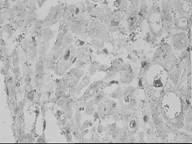

Полученные нами данные отличаются от таковых в литературе. Хотя обнаруженное нами окрашивание части ядер белка bcl-2, локализующегося на внутренней митохондриальной мембране, отмечено и в некоторых эксперимантальных исследованиях (на крысах) (Xie. 2001), продукт реакции в ядрах был выявлен. В цитоплазме кардиомиоцитов определялась слабая и умеренная реакция. В общем можно заключить, что имеет место очень слабая экспрессия bcl-2 в кардиомиоцитах, без существенных различий между обеими группами.

Обсуждение. Данные, полученные нами, сопоставлять с литературными довольно трудно, в пользу этого говорит также окрашивание части ядер белка bcl-2, который локализуется на внутренней митохондриальной мембране, хотя можно сказать, что это обнаружилось в некоторых экспериментальных исследованиях (на крысах, Xie, 2001). В цитоплазме кардиомиоцитов определялась слабая умеренная реакция. В общем можно полагать, что имеет место очень слабая экспрессия кардиомиоцитов без существенной разницы в II группе пациентов. Таким образом, можно сказать, что на данном материале получена закономерная зависимость между экспрессией bcl-2 и p-53, что при малом количестве p-53 положительных клеток можно было видеть большое количество bcl-2 и наоборот.

Рис. 4. В цитоплазме кардиомиоцитов слабая реакция на bcl-2